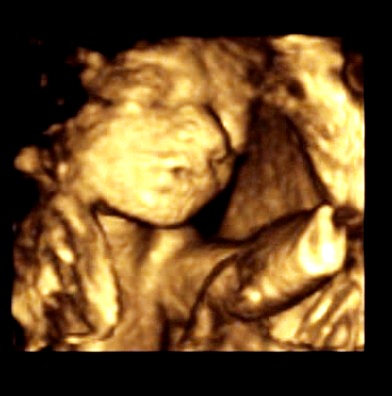

5.10.2010 - 1.UZ v poradně - 7.tt - Srdíčko krásně bije.

19.10.2010 - 2.UZ v poradně - 9.tt Fazolka má 11,1mm. Máme první foto.